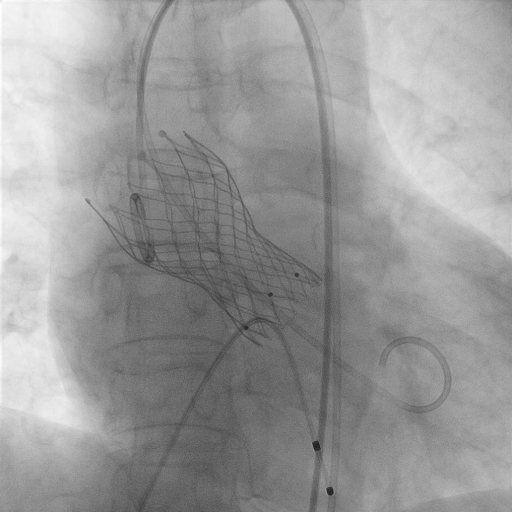

△TAVR术后影像

10月17日,在麻醉科、超声科等多学科团队的协同配合下,心血管内科手术团队精准操作,顺利为患者植入人工主动脉瓣。术后复查显示,瓣膜功能良好,心脏泵血能力显著提升,患者胸闷、心悸症状完全消失,活动能力恢复正常。